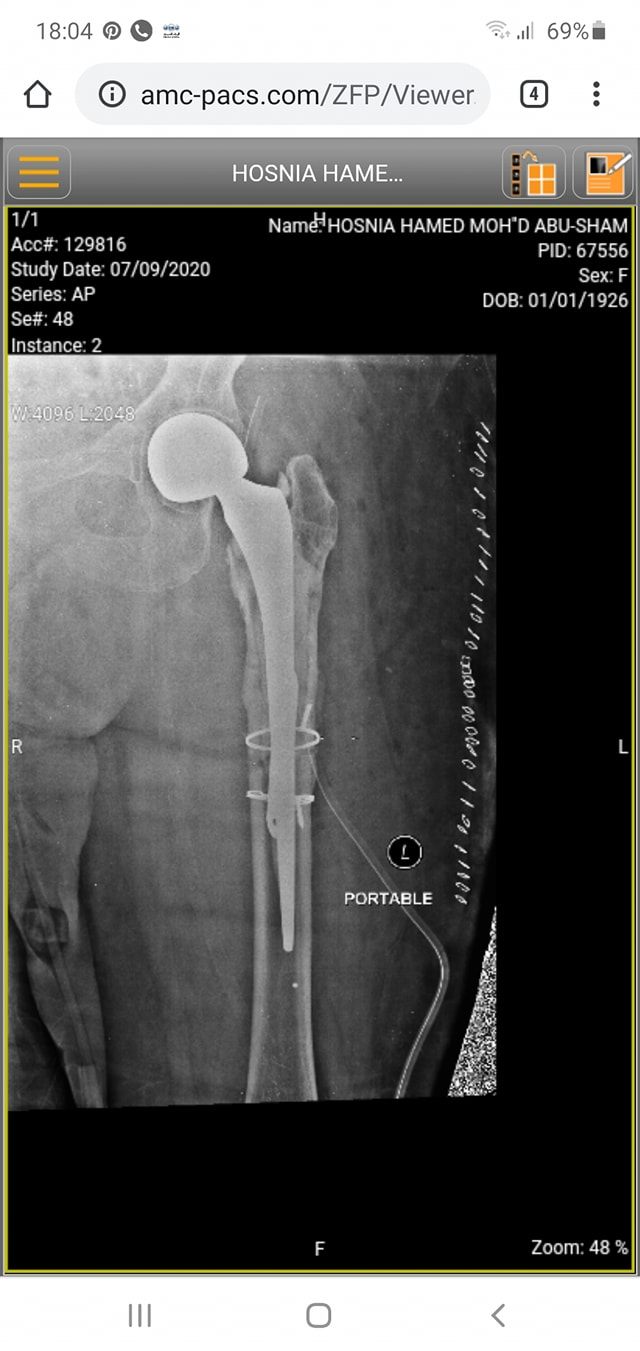

زراعة المفاصل الصناعية ورك و

كافة انواع الكسور وعلاجها